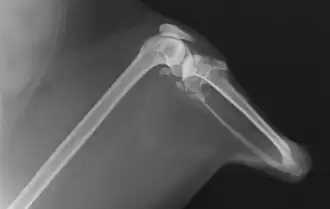

Röntgenaufnahme (2013) -